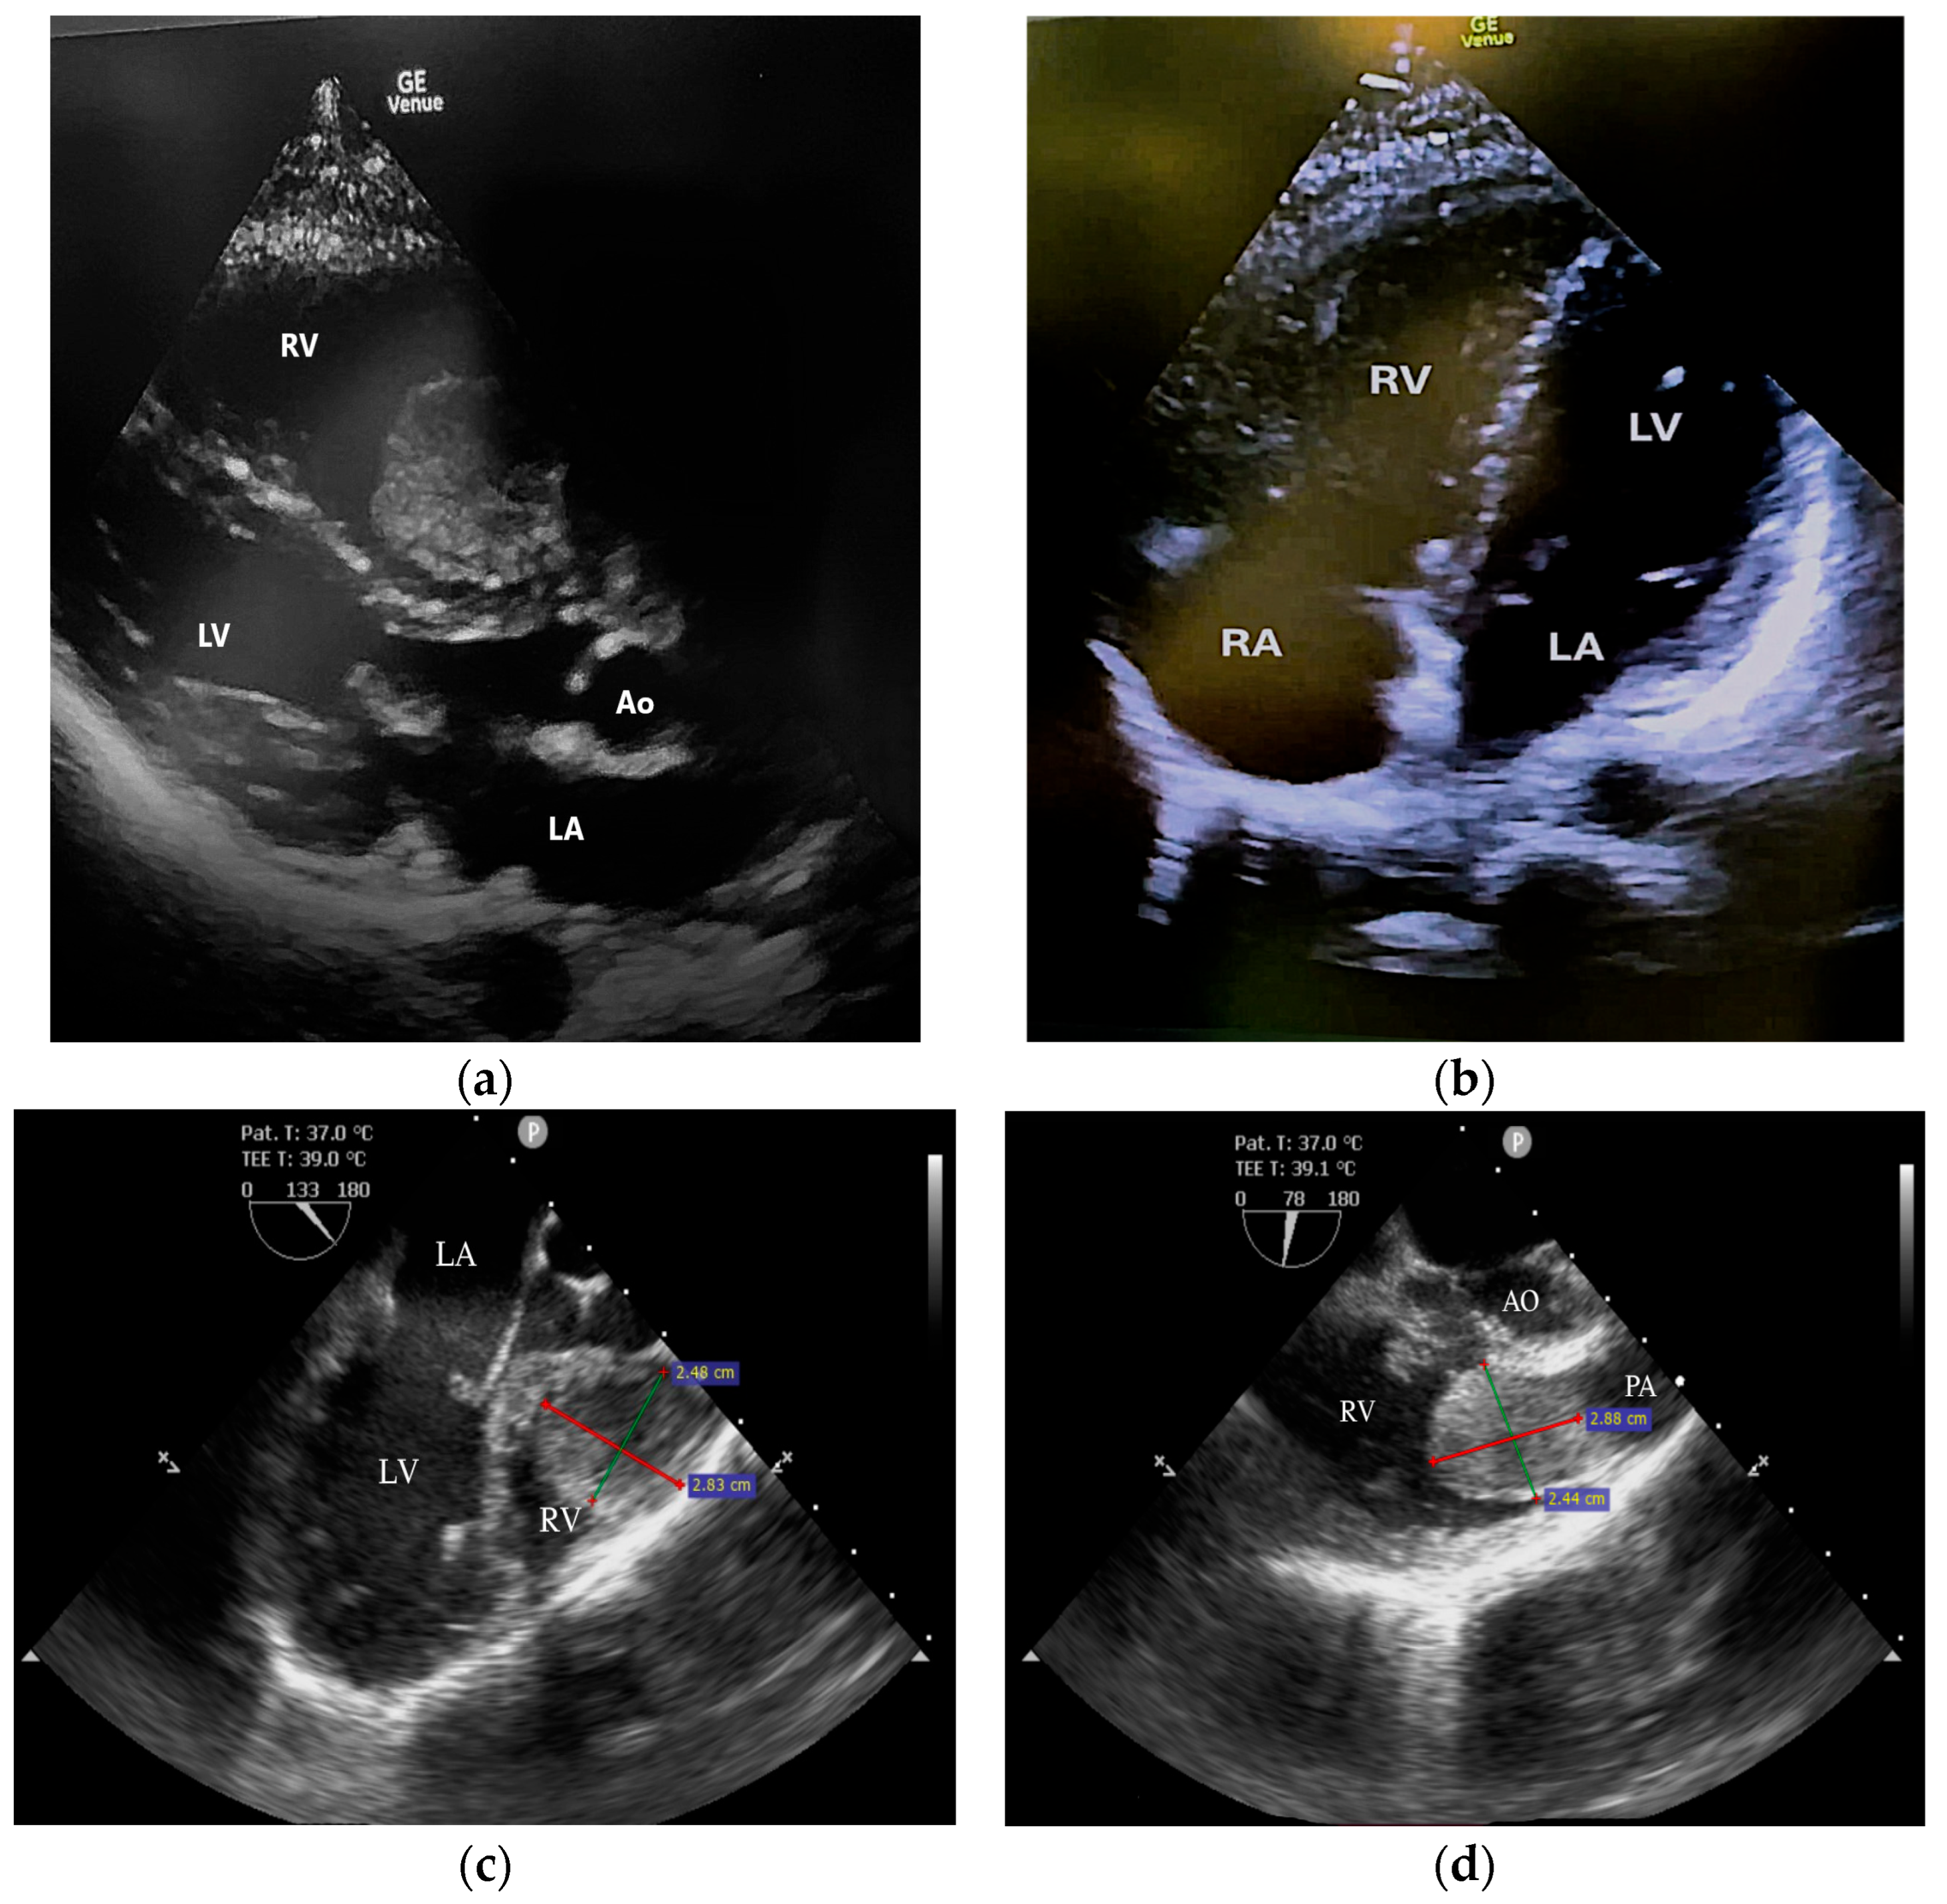

2. Case Report